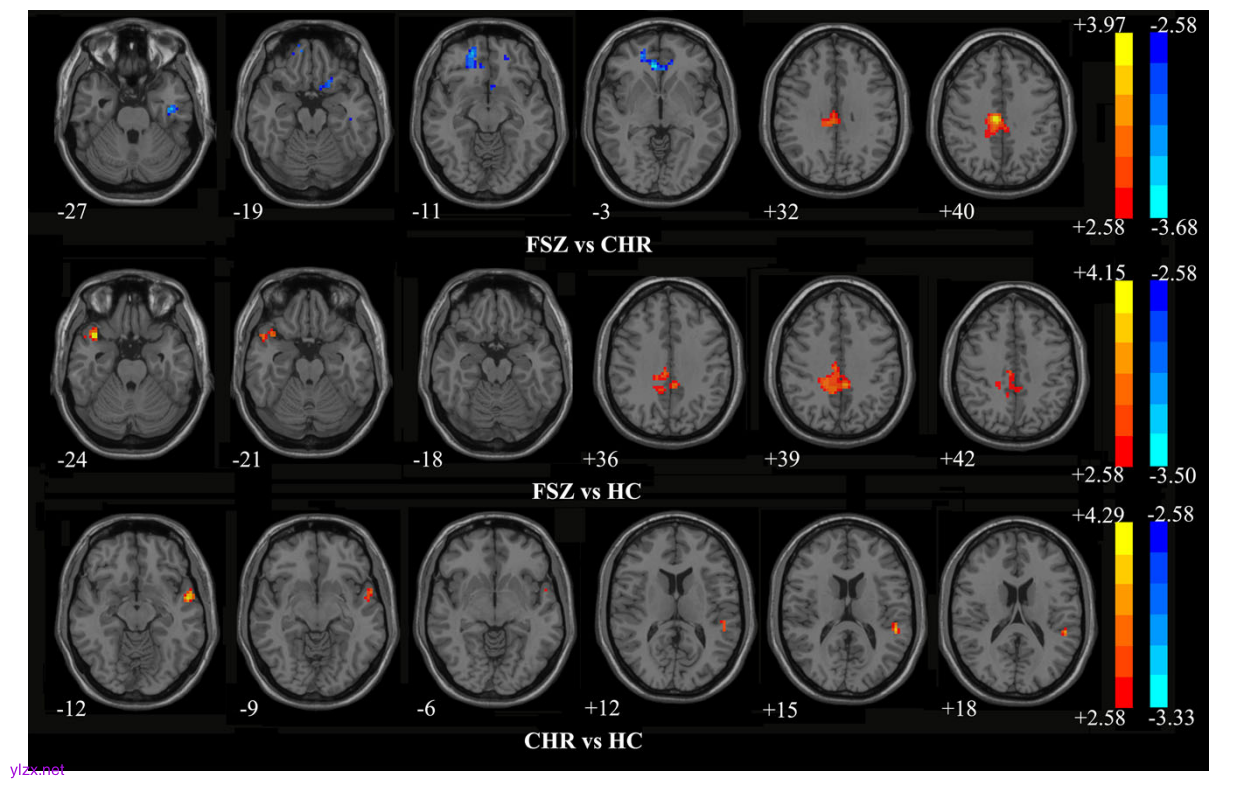

图1:FSZ、CHR和HC组间ReHo差异

研究结果显示,FSZ患者在自由观看、平滑追踪和注视稳定性任务中表现出广泛的眼动异常,包括扫视幅度、速度和扫描路径的显著降低,而CHR个体在自由观看和注视稳定性任务中表现出部分异常,但程度较轻。脑功能分析发现,FSZ患者的右侧中扣带回(MCC)和颞极(STP)ReHo值显著升高,而CHR个体的左侧颞中回(MTG)和颞上回(STG)ReHo值升高。这些异常脑区与眼动参数存在相关性,例如左侧STG的ReHo值与平滑追踪任务中的扫视次数呈正相关。机器学习分类表明,结合眼动和ReHo特征可高精度区分FSZ、CHR和HC,分类准确率最高达94%。基因分析发现,FSZ和CHR的ReHo异常与1639个和1127个基因相关,这些基因富集于突触结构和功能(如钙信号通路和催产素信号通路)中,并在大脑皮层特异性表达。蛋白互作网络分析进一步揭示了CTNNB1、CAMK2A等关键基因在精神分裂症中的潜在作用。